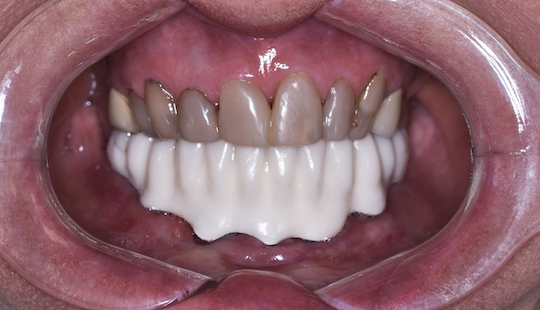

2. Zkouška tvaru a přesnosti v definitivním anatomickém tvaru pomocí bílého resinu nebo frézovaného či tištěného PMMA ✅

Po odsouhlasení přesného dosedu, správného tvaru a skusu zhotovujeme definitivní zubní náhradu 👇

Zkouška přesnosti a tvaru pomocí PMMA

Pomocí PMMA je konečný výsledek Branemarku kompletně předem vyzkoušený a odsouhlasený lékařem i pacientem.

Při odevzdávání tedy nehrozí žádné překvapení.